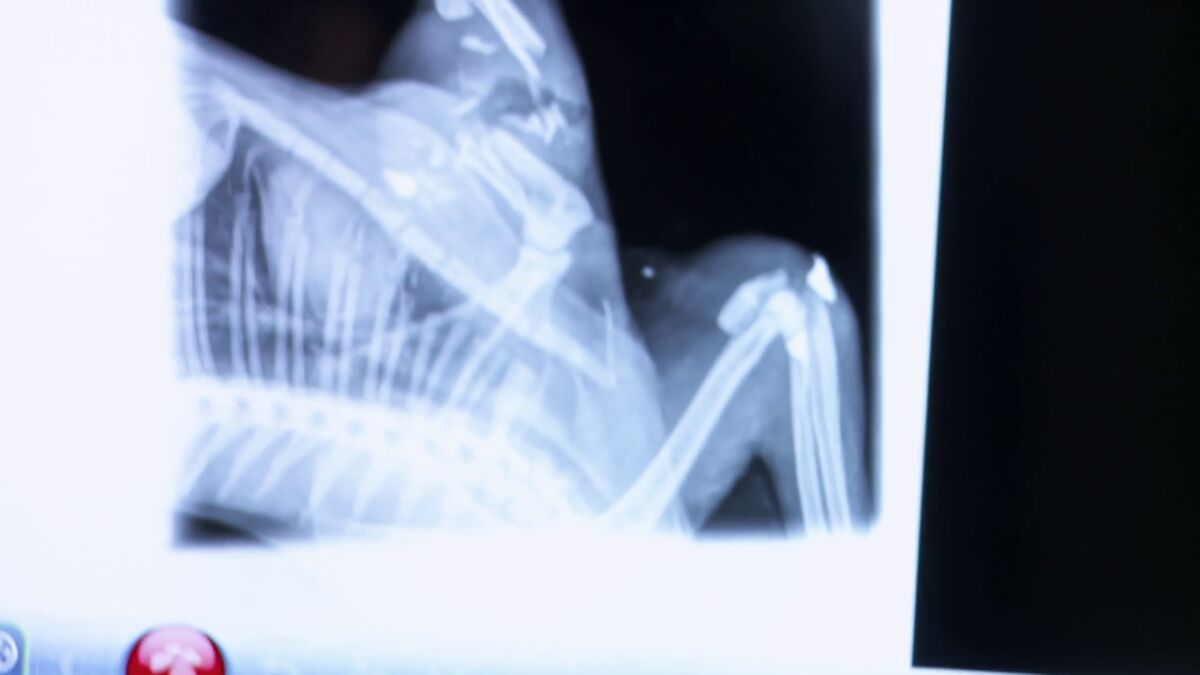

El gato Fredy lleva unas semanas sin poder apoyar la pata derecha y su dueña ha decidido llevarlo a la clínica.

Fredy, un gato doméstico y relativamente joven, llega a la clínica del doctor Pol con una grave afección. Lleva varias semanas sin poder apoyar la pata derecha y los dueños no saben por qué.

Al parecer, tiene que ver con una herida que está en esa misma pata. En un primer análisis, el doctor Pol ha observado que la herida está infectada pero no sabe realmente cuál es el origen, por eso le manda una radiografía.

Tras observar la radiografía el doctor Pol tiene un diagnóstico claro: alguien ha disparado un perdigonazo a Fredy.